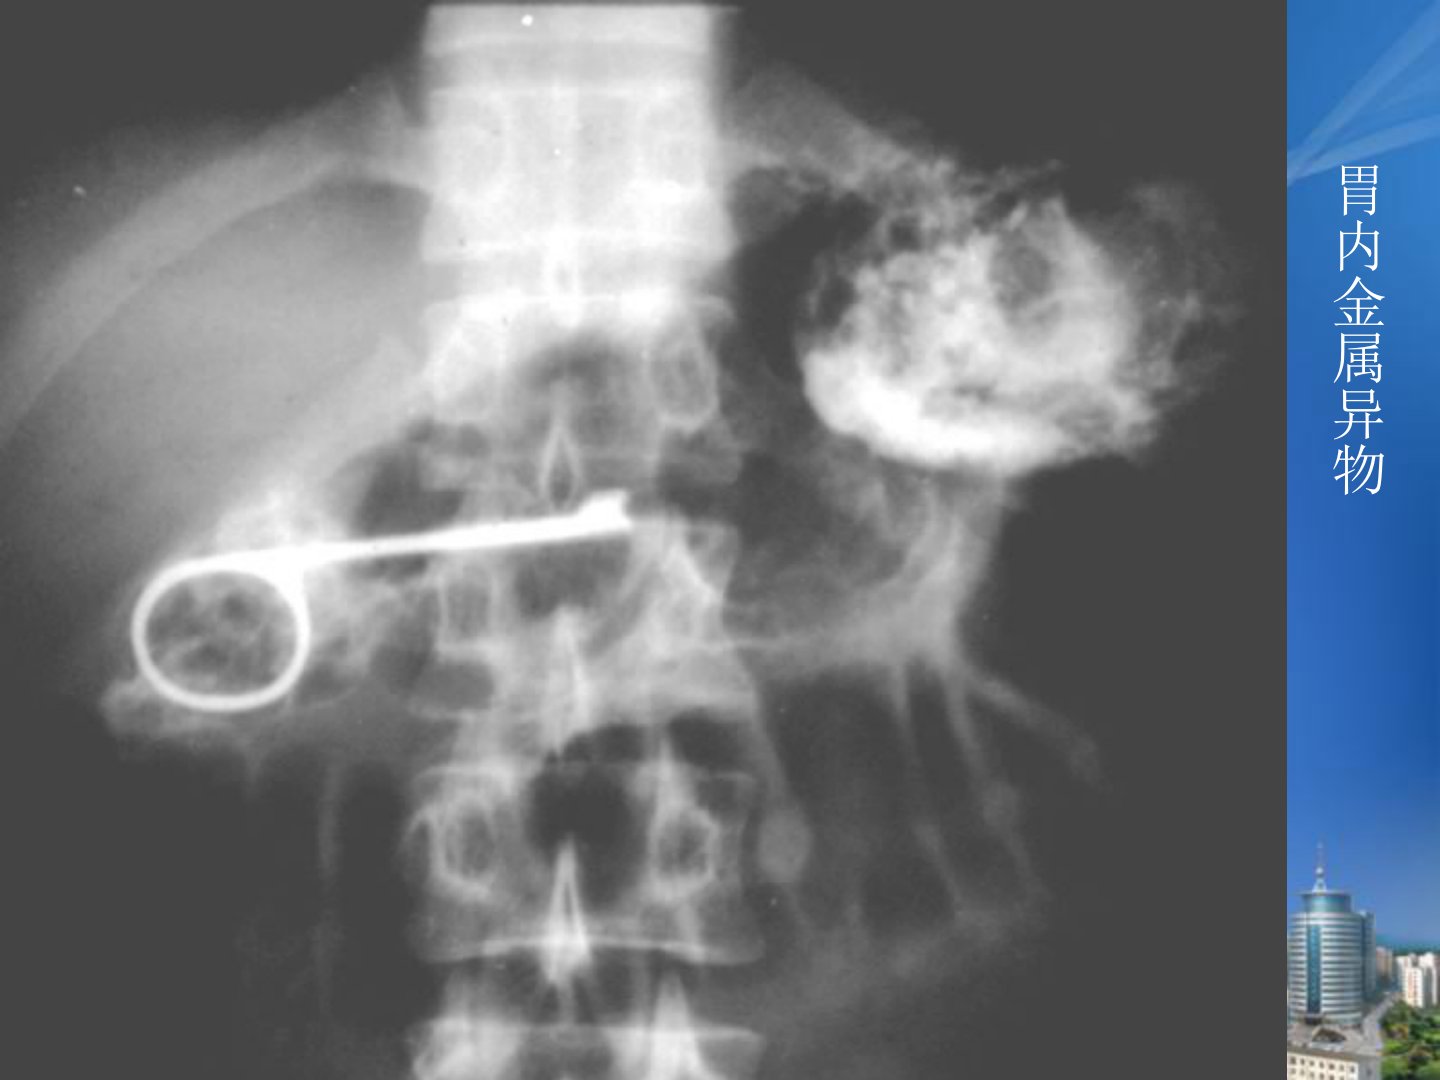

食管胃的常见疾病X线表现胃内金属异物食管癌(一) 临床特征1、 我国常见恶性肿瘤之一,占全消化道肿瘤的53.6%2、 有一定的地区性3、 发病年龄常见于40岁以上,其中50-60岁为发病高峰4、 男性多于女性,男女比例为5∶1左右5、 主要症状是进行性吞咽困难。(一) 病理好发于食管中段,多为鳞状细胞癌,其次是食管下段,以腺癌为主(占少数)早期食管癌:癌肿位于粘膜及粘膜下层,瘤体一般在3cm以内,周围及远处无转移。中晚期食管癌:癌肿侵入肌层,外膜及以外有局部及远处淋巴转移。髓质型:病变范围广,累及食管全层,腔内腔外同时生长,管壁增厚,管腔狭窄蕈伞型:亦称增生型、息肉型、结节型。病变累及管壁...